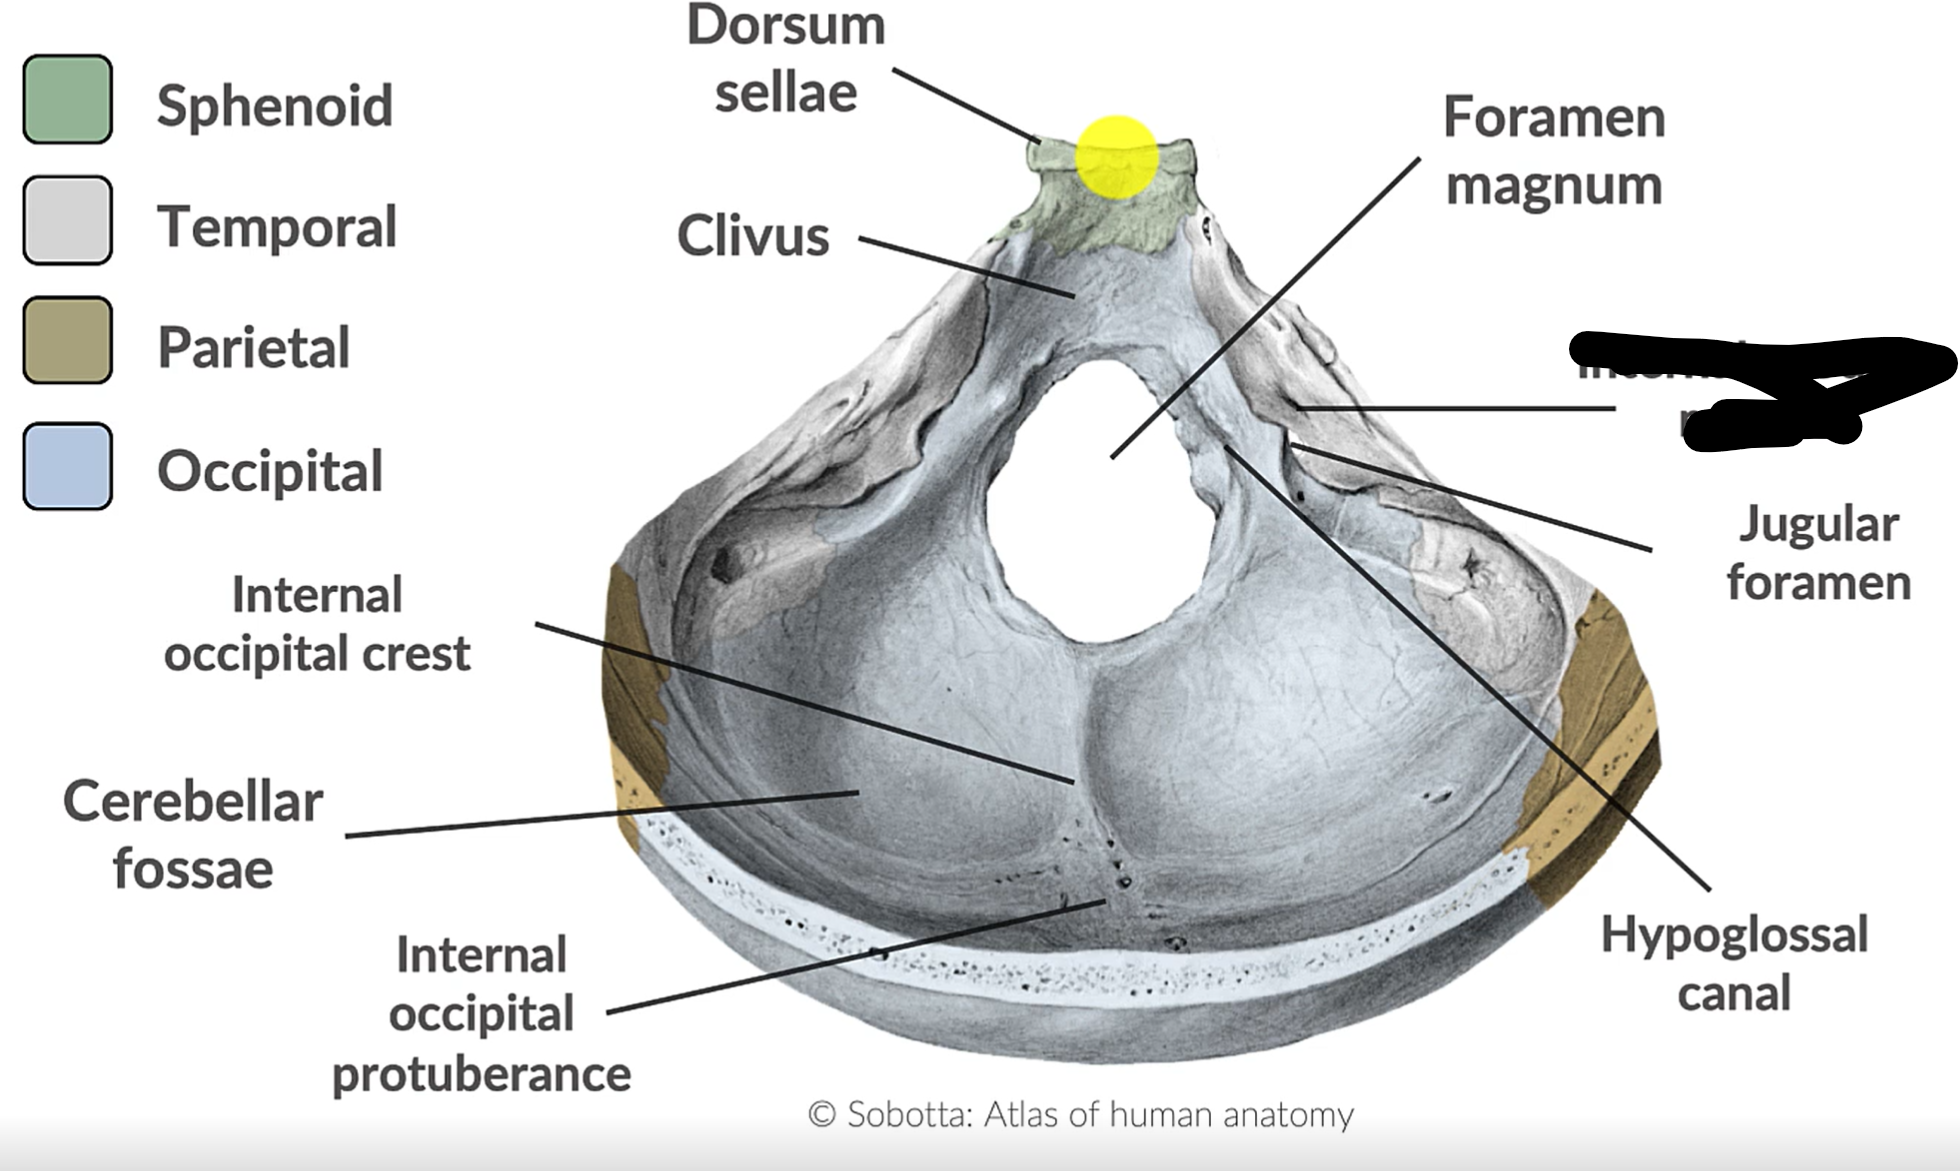

What forms the posterior cranial fossa?

Occipital, temporal, parietal and sphenoid bones

Foramen magnum

Jugular foramen

Internal acoustic mediatus

Hypoglossal canal